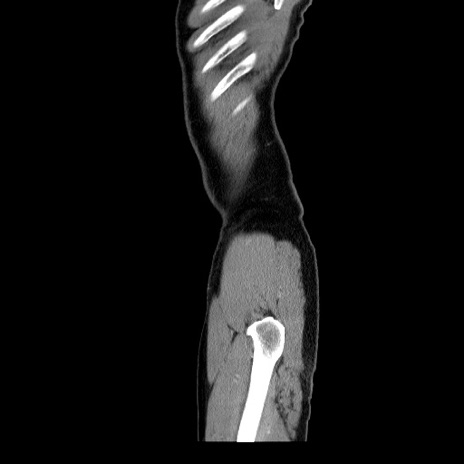

【症例】60歳代 男性

【主訴】右鼠径部膨隆

【現病歴】1年程前より右鼠径部膨隆あり。自己にて還納可能だったため放置していた。3時間前より右鼠径部の脱出を認め、還納困難となり受診。

【身体所見】右鼠径部に小児頭大の膨隆あり。弾性硬であり、用手還納は困難。左鼠径部にも膨隆を認める。脱出はなし。